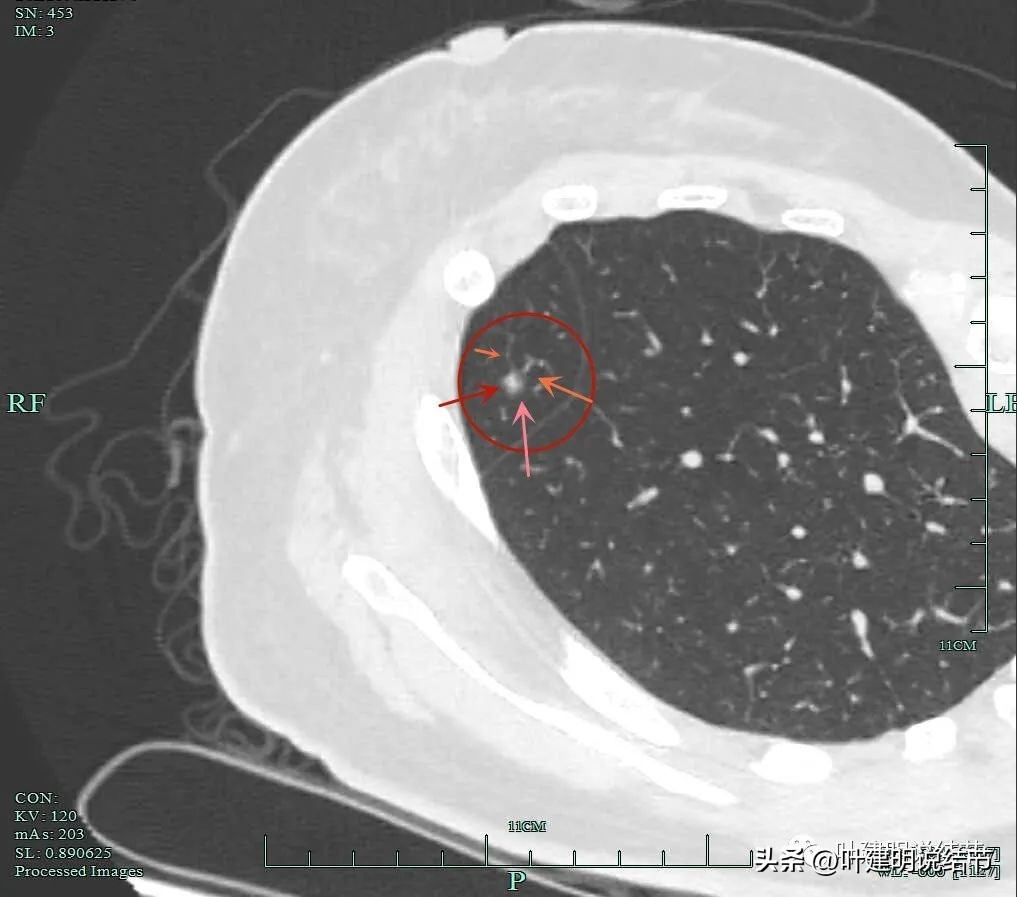

平扫上病灶位置右中叶,较小,但密度并不低,是混合磨玻璃的样子。

甚至有微血管进入的表现。

靶扫描重建图像显示了病灶明显的血管进入(如桔色箭头所示),灶内似见进入血管的穿行,而且显得毛糙与异常增粗。

微小血管进入明显且多处;粉色箭头示病灶内部偏实性成分也明显。